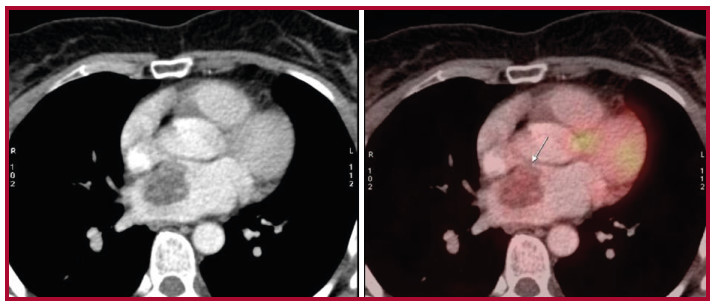

La paciente es evaluada por el servicio de Reumatología, que diagnostica espondiloartropatía inflamatoria con marcadores inflamatorios persistentemente elevados sin cumplir criterios de enfermedad reumatológica, por lo que se solicita tomografía por emisión de positrones (PET) que evidencia tumor único en aurícula izquierda (Figura 1).

Por ello se decide realizar una tomografía que evidencia masa en la aurícula izquierda en contacto con el septum interauricular de 30 × 22 mm, de densidad heterogénea, con bordes regulares, con realce luego de la administración de contraste endovenoso, sin evidencia de invasión de venas pulmonares. Se interpreta como posible mixoma auricular, por lo que se decide resección quirúrgica. Se realiza abordaje transeptal, se reseca tumoración de 5 cm sin complicaciones y se envía muestra a Anatomía Patológica.